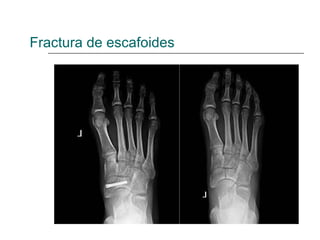

Fractura de escafoides

• #22 Fractura luxación del escafoides tarsiano, el astrágalo se coloca entre los dos fragmentos de escafoides provocando un acortamiento del arco interno y un pie plano. Si existe desplazamiento de mas de 2mm hacer reducción y osteosintesis. Resto tto conservador yeso de 6-8 s. Fracturas de estrés típicas en atletas. Tto conservador Hacer diagnostico diferencial hueso accesorio navicular (10%)